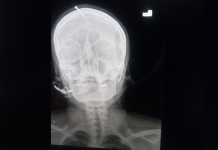

Беременная женщина в Пакистане вбила гвоздь себе в голову, чтобы родить мальчика

Жительница города Пешавар (Пакистан) так сильно хотела сына, что обратилась за помощью к целителю. Тот посоветовал ей забить гвоздь в лоб, чтобы пол ребенка точно была...